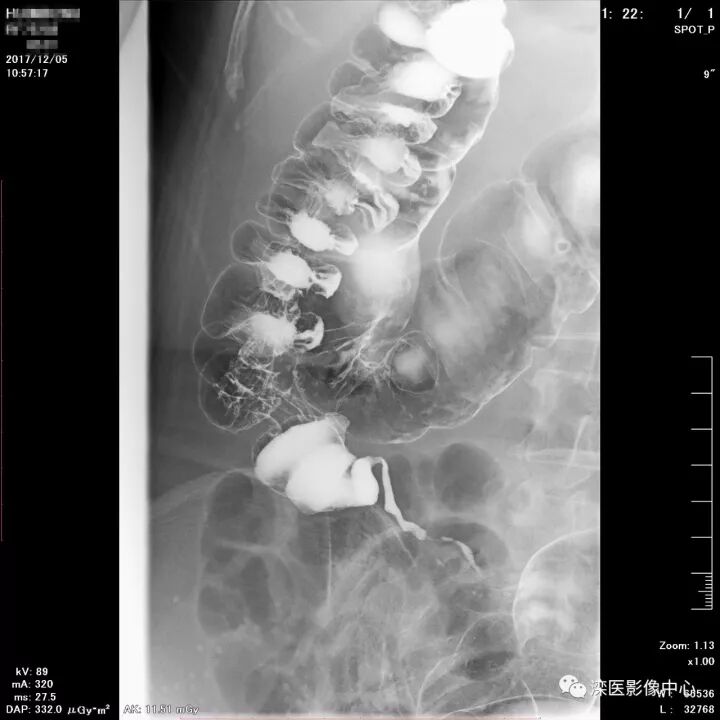

下面请您审阅近期我院影像科开展下消化道双对比造影检查的图像:

(以上图像是对显示降结肠的显示